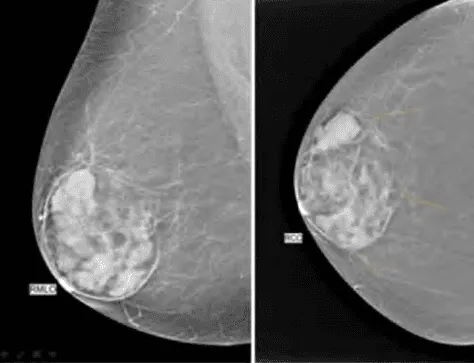

Phần tiêu đề “Cận lâm sàng”Hình ảnh “(Trái, trên) Siêu âm bướu sợi-tuyến: Khối giảm âm, bờ đa cung, đồng nhất. (Trái, dưới) MRI bướu sợi-tuyến: giới hạn rõ, đồng nhất, có vùng thoái hóa. (Giữa) Nhũ ảnh MLO: khối có lớp mỡ mỏng bao quanh. (Phải) Hình ảnh đại thể bướu sợi-tuyến: vỏ bao rõ, mặt cắt phồng đồng nhất”.

Siêu âm:

- Khối giảm âm đồng nhất, bờ rõ, đôi khi có múi, thành trước dày, tăng âm phía sau (posterior acoustic enhancement).

- Hình dạng: Hình tròn hoặc bầu dục, chiều dài lớn hơn chiều ngang (định hướng song song với da).

Nhũ ảnh:

- Khối hình tròn/bầu dục, bờ sắc nét, có thùy nhẹ, không xâm lấn mô xung quanh.

- Thường bao quanh bởi vầng sáng mỏng (halo) do mô mỡ - đặc trưng cho khối lành tính.

- Đôi khi thấy vùng thấu quang bên trong do thoái hóa mỡ.